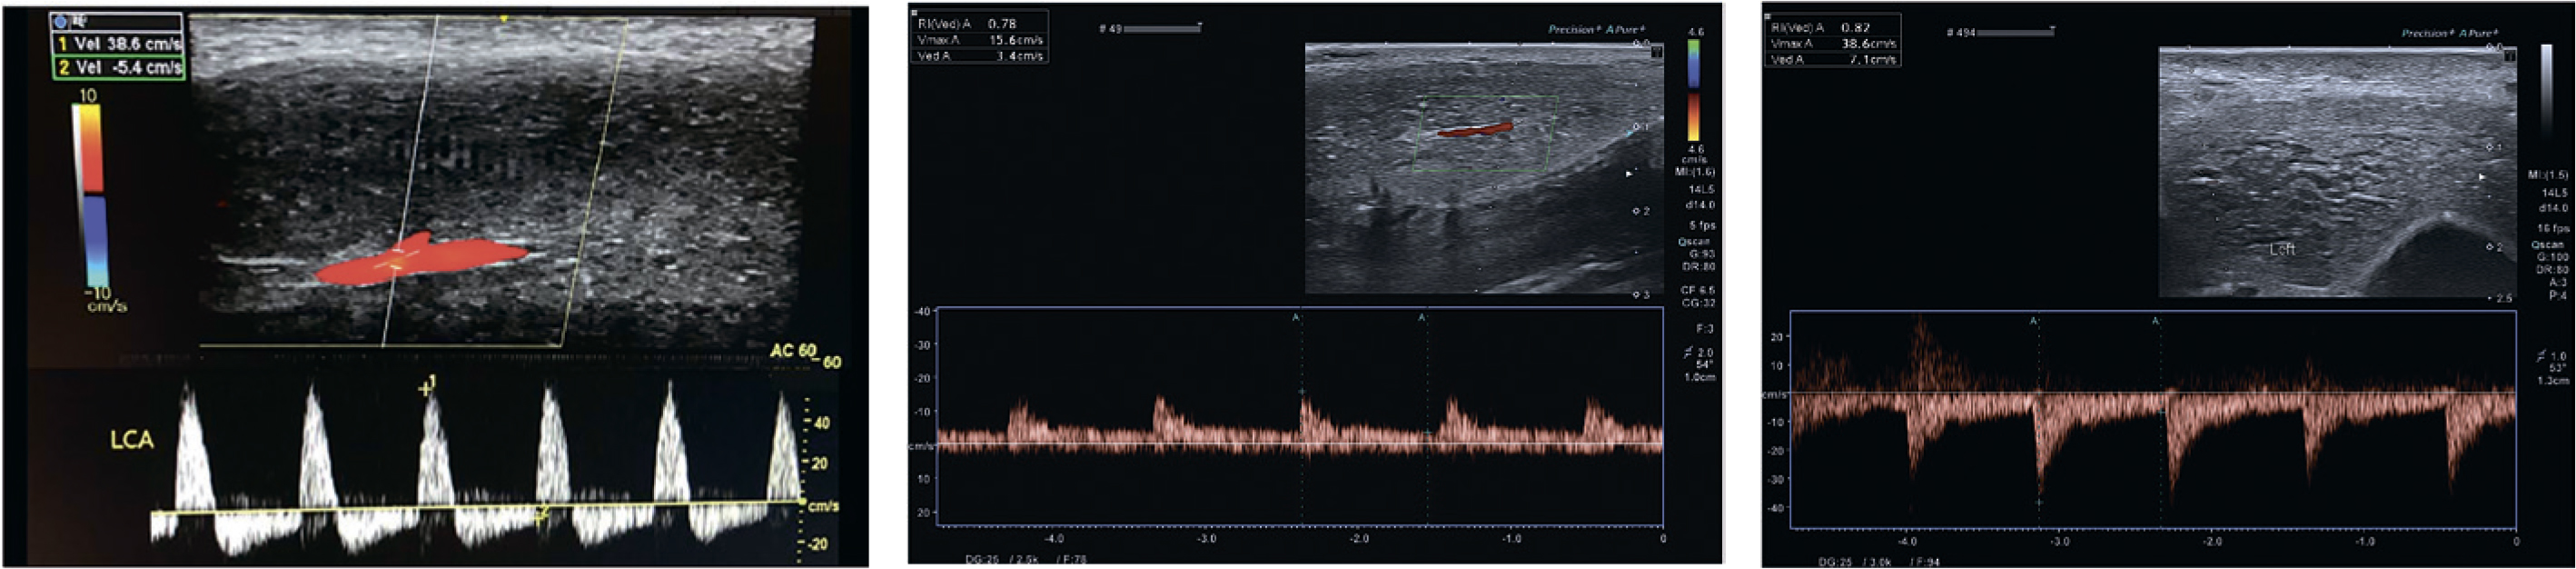

Нулевая EDV или ретроградный кровоток в диастолу (отрицательные значения EDV) свидетельствуют об отсутствии венозной и корпоровенозной ЭД.

Рис. 1. Нормальная допплерограмма с ретроградным кровотоком в диастолу. Отсутствие признаков васкулогенной дисфункции

Рис. 2. Допплерограмма с признаками артериогенной эректильной дисфункции

Рис. 3. Допплерограмма с признаками веногенной эректильной дисфункции